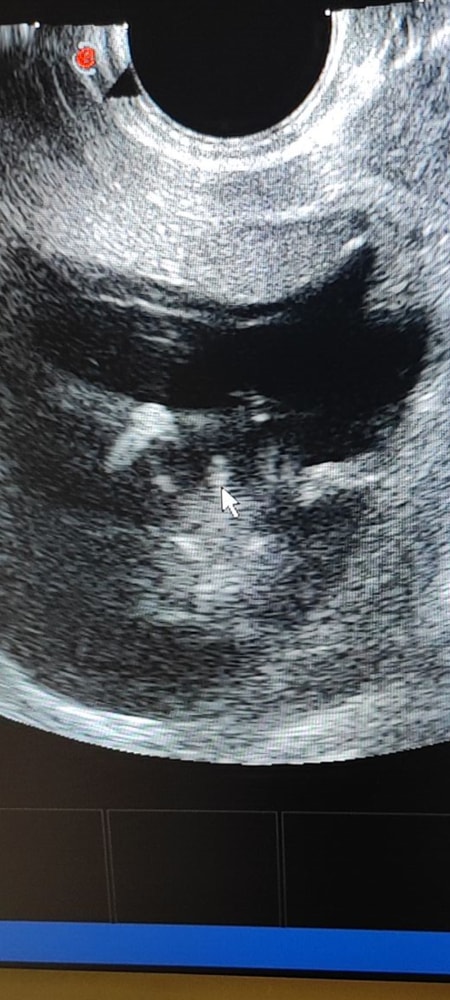

Затрудняюсь с категориейВсем привет! Срок 12 недель, завтра первый скрининг. Сегодня утром встала, после похода по маленькому на бумаге коричневая кровь. Я в панике, думаю ехать ложиться в стационар, но как, завтра же такой важный день, первый скрининг! В общем уехали с сыном в другой город за 60 км к лору, и пока ехали записалась сегодня на узи, думаю если что, узистка скажет что делать, ехать в стационар или терпеть до завтра. И кстати вот эта утренняя кровь на бумаге, была разовая акция, тьфу тьфу тьфу, потом все чисто. Приехали обратно с сыном, я бегу на узи. Слава богу все хорошо, хорион немного перекрывает зев, от того иногда может идти коричневая кровь. Девочки, приложу фото пипирки (там, где стрелка от мышки), узистка говорит мальчик)) но вроде как в 12 недель у них просто половой бугорок, и не поймешь пол ребенка?